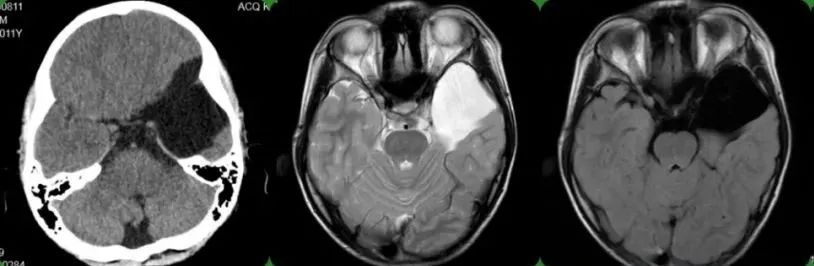

MRI如图所示: